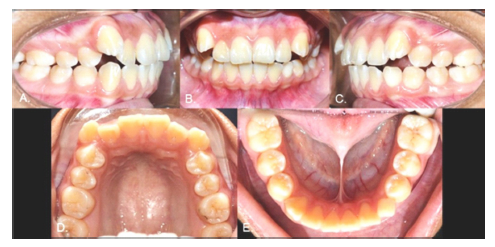

Case 2

Female, 15 years old. As with Case 1, the inferior left canine was the only primary tooth remaining in the mouth (Fig. 3). The radiograph showed that the 3.3 exhibited a type 2 transmigration (Figs. 4, A and B). The tooth was located closer to the mandible edge than in Case 1, precluding the use of orthodontic traction, and it was decided to monitor the tooth. Dental protrusion was the initial reason for the appointment, and the patient requested orthodontic treatment of this condition. Because the 3.3 was far from the roots of the neighboring teeth, the orthodontist decided there would be no risk in moving teeth in this zone. To correct the protrusion, the first premolars were extracted (except for quadrant 3 since the 3.3 was transmigrated). The 3.3 would not be restored in this treatment since the 3.4 would take its place. The 1-year follow-up panoramic x-ray showed no significant changes (Fig. 4C).